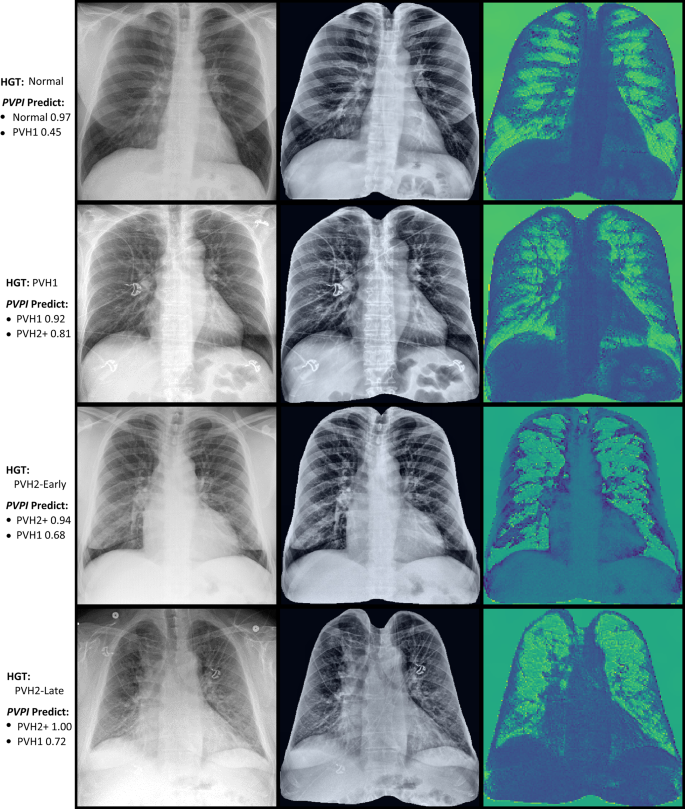

PVPI activity maps [Fig. 2] demonstrated an increasingly redistributed balance of activity (green) from lung bases to upper-lung regions with worsening HGT-assigned PVH Stage; for each example, the highest PVPI PVH-Ranking prediction (PVH Predict) corresponded well with HGT PVH-Staging assignment. However, with both the pulmonary vasculature and cardiac silhouette reflecting relative inactivity (blue shades), changing physiological “States” rather than PVPs were apparently recognized by the PVPI.

PVPI activity maps.